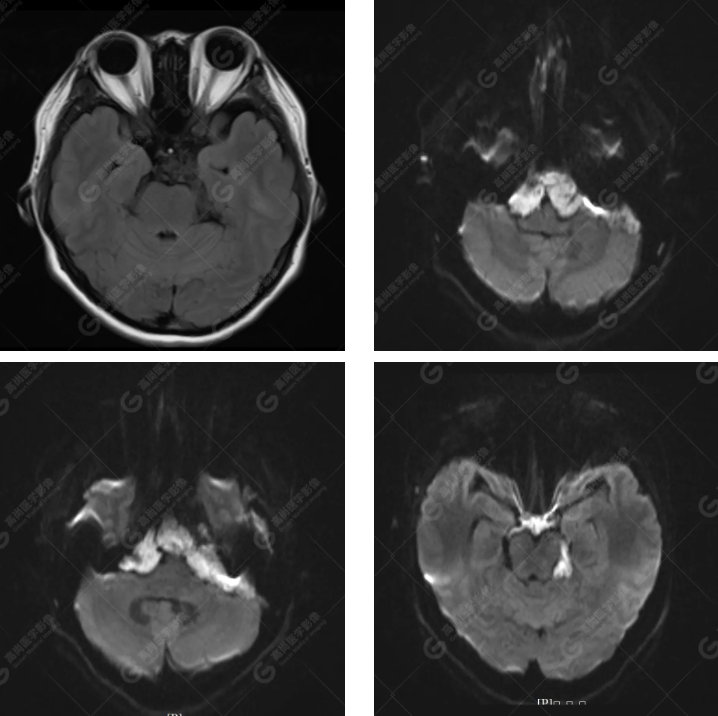

MRI 影像所见:

延髓池、桥前池、双侧桥小脑角区、鞍上池至左侧小脑幕下见团片状异常信号影,呈长 T1 长 T2 信号,FLAIR 序列呈不均匀稍低信号,DWI 序列呈高信号,ADC 图低信号,增强后无强化。右侧面听神经受压向后移位,双侧三叉神经及左侧面听神经被包埋,显示不清。

延髓池、桥前池、双侧桥小脑角区、鞍上池至左侧小脑幕下胆脂瘤,右侧面听神经受压向后移位,双侧三叉神经及左侧面听神经被包埋

MRI 表现为 T1WI 呈略高于脑脊液的低信号,T2WI 呈均匀高信号,信号接近于脑脊液,T2-FLAIR 序列上病灶信号未完全被抑制高于脑脊液,DWI 高信号,ADC 低信号(具一定特征性)。